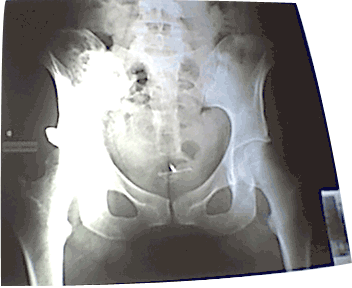

the x-ray with the IntraUterine Device

Amongst other personal artifacts exhibited, was her Intra Uterine Device.

IUD also known as a "Copper-T" and in dutch as a "Spiraaltje".